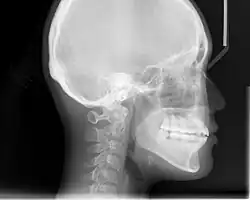

An X-ray taken for skull analysis

In the postwar period, cephalometric radiography[14] started to be used by orthodontists for measuring changes in tooth and jaw position caused by growth and treatment.[15] The x-rays showed that many Class II and III malocclusions were due to improper jaw relations as opposed to misaligned teeth. It became evident that orthodontic therapy could adjust mandibular development, leading to the formation of functional jaw orthopedics in Europe and extraoral force measures in the US. These days, both functional appliances and extraoral devices are applied around the globe with the aim of amending growth patterns and forms. Consequently, pursuing true, or at least improved, jaw relationships had become the main objective of treatment by the mid-20th century.[8]